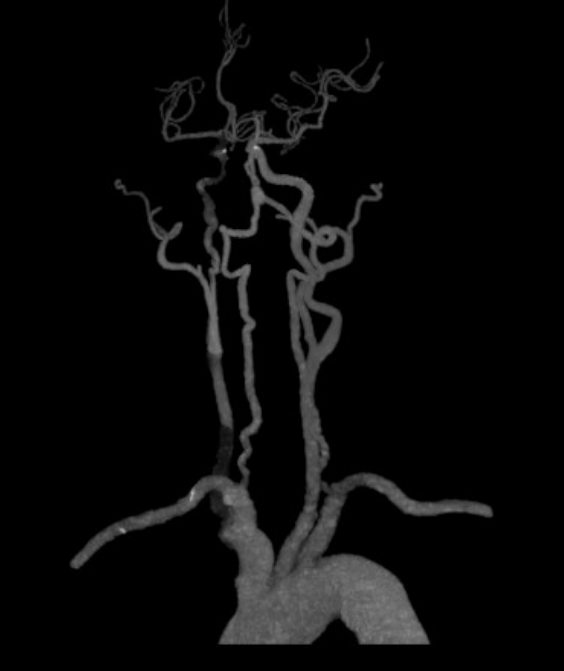

患者抵达后,急诊团队马上运行危重症救治经过,立即完善头颈CTA及颅脑MR查验,着力进一步明确:主动脉夹层;右颈总动脉、右颈内动脉长节段未见显影,探讨夹层累及或假腔血栓变成;右侧大脑半球分水岭脑梗死,灌输减低。

△头颈CTA教导右颈总动脉长节段未见显影,探讨夹层累及或假腔血栓变成。